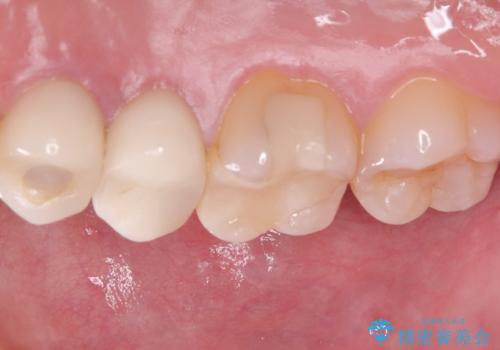

補綴物は残存歯質量からクラウンとしました。

・生活歯髄療法 40,000円(税抜き)

・仮歯 10,000円(税抜き)

・オールセラミッククラウン(スタンダード)110,000円(税抜き)